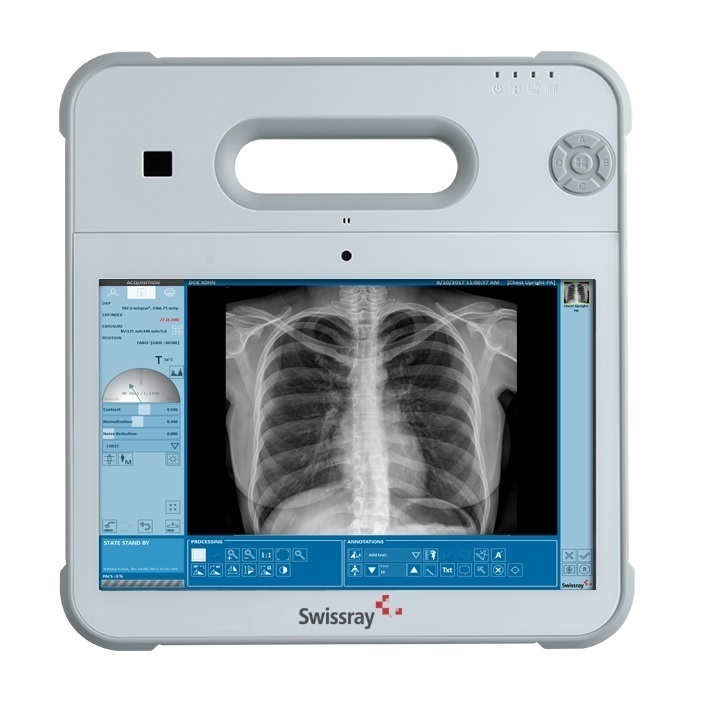

The lightweight and rugged 10” ddRAura™ Drive Kit mobile tablet based workstation can be used with any analog room or mobile x-ray system utilizing the auto – detection functionality of the flat panel detector to acquire images from any x-ray source. The tablet can also be docked and connected to a full screen monitor.